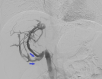

A young adult male was referred for a second opinion of deranged liver biochemistry. He initially presented two years prior with abdominal pain, lethargy and fevers due to a segment two pyogenic liver abscess. He received empirical antibiotic therapy to resolution. Computed tomography for abscess follow-up revealed an intrahepatic inferior vena cava thrombus. He was anti-coagulated with warfarin. He was lupus anticoagulant positive and had a highly positive beta-2 glycoprotein antibody on serial measurement and was diagnosed with anti-phospholipid syndrome. On current review, the patient had no clinical stigmata of chronic liver disease. There were dilated veins on the supraumbilical abdominal and chest walls. There was mild hepatomegaly but no splenomegaly. Laboratory investigations revealed mildly cholestatic liver function tests with hyperbilirubinaemia (40μmol/L) but no liver synthetic dysfunction. Serological screening did not reveal any cause of chronic liver disease. The patient underwent multiphase abdominal CT and formal hepatic venography. What is the diagnosis and describe the hepatic venous outflow?